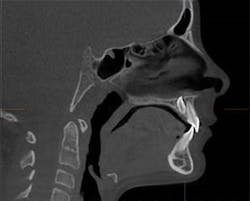

In between Phase I and II of treatment, the office purchased an i-CAT FLX V-Series to replace their 2D panoramic system. For an 8-year-old female, who presented for orthodontic treatment to Dr. Greg Greenberg’s office in Frisco, Texas, that decision provided clarity to a treatment plan and a less invasive option for this young patient.

Prior to starting Phase II, a Cone Beam CT with the i-CAT FLX QuickScan protocol was utilized. The 3D scan of the patient allowed for precise visualization of an inverted and impacted mesiodens located palatal to the central incisors that was difficult to see and was initially overlooked on the 2D panoramic image.

Thus, the ability to visualize the mesiodens in three dimensions and recognize that it was not immediately affecting the permanent dentition was tremendously advantageous to the evolving treatment plan. Close follow-up without intervention was elected in this situation.